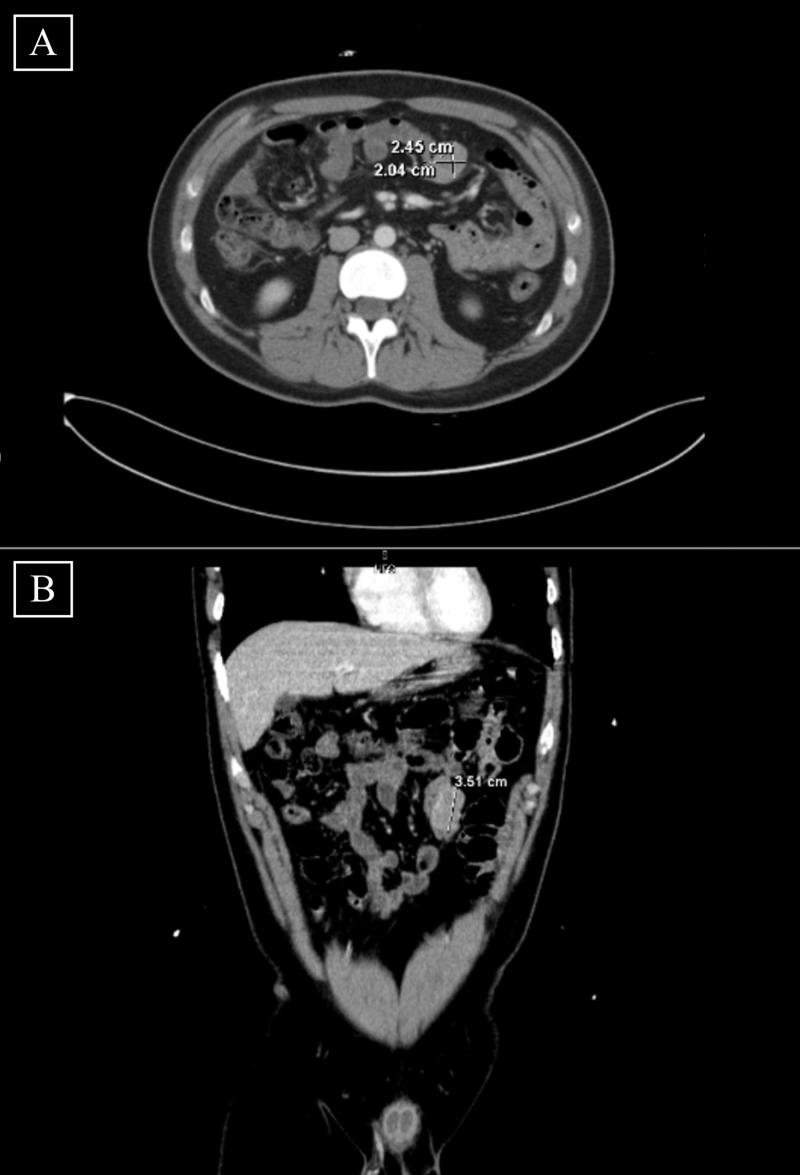

Individuals with neurofibromatosis type 1 are much more likely to develop gastrointestinal stromal tumors than those without this condition. The median age for patients with neurofibromatosis type 1-associated gastrointestinal stromal tumors is approximately 65 years. We present a case of a young male with a history of neurofibromatosis type 1 who presented with symptomatic anemia and melena and was ultimately found to have a gastrointestinal stromal tumor.

1型神经纤维瘤病患者比没有这种疾病的人更易患胃肠道间质瘤。1型神经纤维瘤病相关胃肠道间质瘤患者的中位年龄约为65岁。我们报告一例有1型神经纤维瘤病病史的年轻男性病例,该患者出现症状性贫血和黑便,最终被发现患有胃肠道间质瘤。